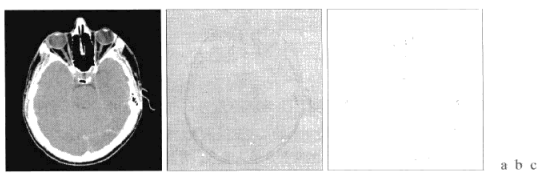

a是低对比度图像,b是直方图均衡后的结果,c是基于规则的模糊集合的对比度增强的结果。通过比较b和c图片,可知后者色调更好,并且更清晰。

在下图中,a是原图,b是模糊空间滤波的结果,c是灰度标定的结果。c图是通过在K=L-1时执行相关计算得到的,最终结果是c图中灰度值跨过从0到L-1的全部灰度级。